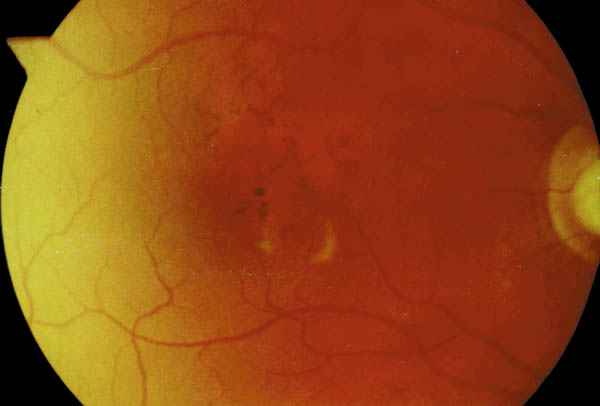

Figura 5

FONDO DE OJO DERECHO DEL PACIENTE 2.